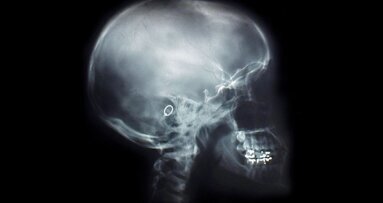

Decyzją zarządu województwa mazowieckiego projekt ten, prowadzony przez firmę Impomed Centrum otrzyma ponad 1,6 mln zł unijnego dofinansowania. Projekt zakłada stworzenie nowego, autonomicznego modułu laboratoryjnego pozwalającego na opracowanie i wdrożenie technologii hodowli autologicznych ludzkich komórek kości (osteoblastów) w warunkach laboratoryjnych. Pozwoli to w przyszłości szpitalom i klinikom korzystającym z tego rozwiązania na efektywne leczenie złamań, martwicy kości i ubytków kostnych. Technologia będzie wykorzystywana zarówno w ortopedii, jak i chirurgii szczękowej i twarzoczaszki. Umożliwi to prowadzenie efektywnej terapii zmierzającej do pełnej regeneracji komórek kości.

Autorzy prezentują własne obserwacje kliniczne konsolidacji heterogennych przeszczepów bloków korowo-gąbczastych w obrębie ...